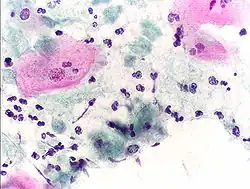

Tinción de Giemsa de un cultivo de T. vaginalis. | ||

- En la preparación citológica con la prueba de Papanicolaou. Se observan estos parásitos de forma alargada, ya sea aisladamente o agrupados en forma de corona, parasitando las células epiteliales, tal como se muestra en la siguiente imagen. En este caso, además de las tricomonas, se puede apreciar una infección por Gardnerellas vaginalis. ("clue cells" sobre las superficies celulares).[3]